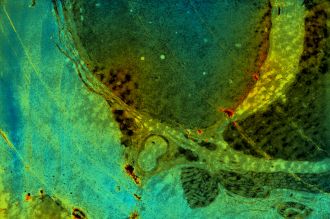

La Trobe University researchers have led a four-year collaboration to make “the invisible visible” by using custom-designed nanomaterials to enhance the sensitivity of phase contrast microscopy, an imaging technique commonly used by scientists to study biological specimens.

Project leader and La Trobe Institute for Molecular Science (LIMS) physicist, Professor Brian Abbey, said the discovery allows scientists to detect minute changes in the composition or structure of transparent or nano-thin objects, enabling their key features and structures to be visible when put under a microscope.

“Features that were previously impossible to detect using conventional techniques can now be imaged using our microscopy method, developed by lead author and La Trobe Senior Research Fellow Dr Eugeniu Balaur,” Professor Abbey said.

“This technique allows scientists to examine cells in their natural state without previously being stained or labelled. As a result, their structure and function – and perhaps even their dynamics – can be better understood,” Professor Abbey said.

“We now have the tools to manipulate matter at the nanoscale. Our custom designed nanomaterials have enabled us to achieve a huge leap forward in terms of image quality and contrast, building on the groundbreaking phase work of Zernike in the 1930s.”

“The technique the team developed enables us to perform label-free imaging of cellular structures with exceptional contrast and in their natural state. Coupling nanotechnology with phase contrast microscopy lays the foundation for entirely new fields of research and represents a significant leap forward for the life sciences," Dr Nicholas Anthony, study co-author from the Istituto Italiano di Tecnologia (IIT) said.